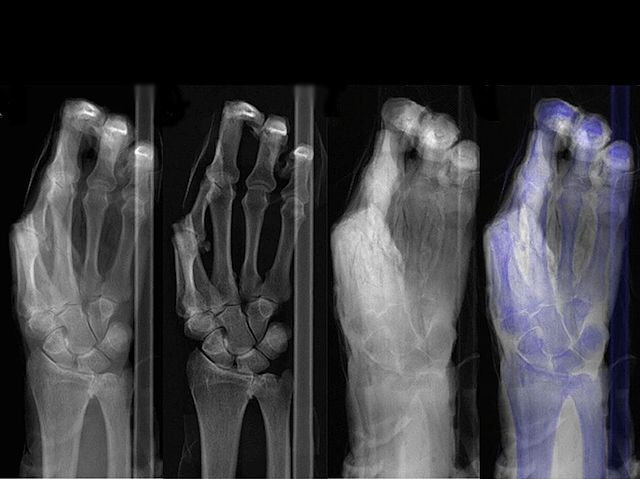

Dual-energy radiography can better distinguish bone and soft tissue to reveal minor fractures more clearly than standard X-rays

A burst of X-rays fired at a cadaver’s hand – passing through the skin at 186,000 miles per second, invisible to the eye but casting a black and grey pattern around white bones dense enough to absorb the radiation. Standard X-ray radiography scans, usually known as 'X-rays' (like the one of the left here) are commonplace in hospitals, where they’re used to spot broken bones. Yet minor fractures are sometimes missed, especially when surrounding soft tissue is dense enough to appear similarly coloured to bone. While this hand has no bone breaks, it’s helping to test a different technique – photon-counting dual-energy radiography – where an algorithm helps to distinguish bone (middle left) from surrounding tissue (middle right), presenting a more complete, overlaid picture (right). Radiologists found this more informative than X-rays alone, potentially helping to spot subtle bone injuries that, left untreated, may otherwise lead to conditions like arthritis.